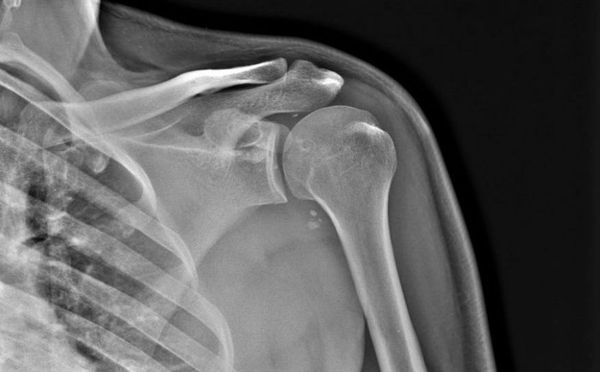

Все началось с того, что мужчина был сбит автомобилем, после чего скорая помощь доставила его в Республиканскую больницу №2 – Центр экстренной медицинской помощи. Там его обследовали нейрохирург, травматолог и гнойный хирург. После рентгена пациенту поставили диагнозы: автотравма; ушиб поясничной области; ушиб мягких тканей левого плеча. Ему рекомендовали лечиться в поликлинике по месту жительства.

Пациент остался недоволен осмотром в РБ №2. И, посчитав свои травмы после аварии более серьезными, в тот же день истец обратился в травматологию медцентра города Якутска. Ему снова сделали рентгеновский снимок, на этот раз диагнозы поменялись с ушибов на – перелом средней трети левой малоберцовой кости со смещением; умеренная клиновидная деформация тел 8, 9 грудных позвонков. Пациенту оформили больничный лист.

У больного никак не утихали сильные боли. Тогда он в третий раз обратился за медпомощью. Ему в третий раз сделали рентген, где подтвердили диагноз, поставленный в медцентре Якутска. Мужчина не поверил и сходил на компьютерную томографию (преимущественно платная услуга). И наконец-то ему был поставлен верный диагноз – компрессионный перелом тел позвонков; умеренная клиновидная деформация тел позвонков, грыжи Шморля; обызвествленная дорзальная протрузия; патологический кифоз ГОП 3 степени; правосторонний сколиоз 1 степени.